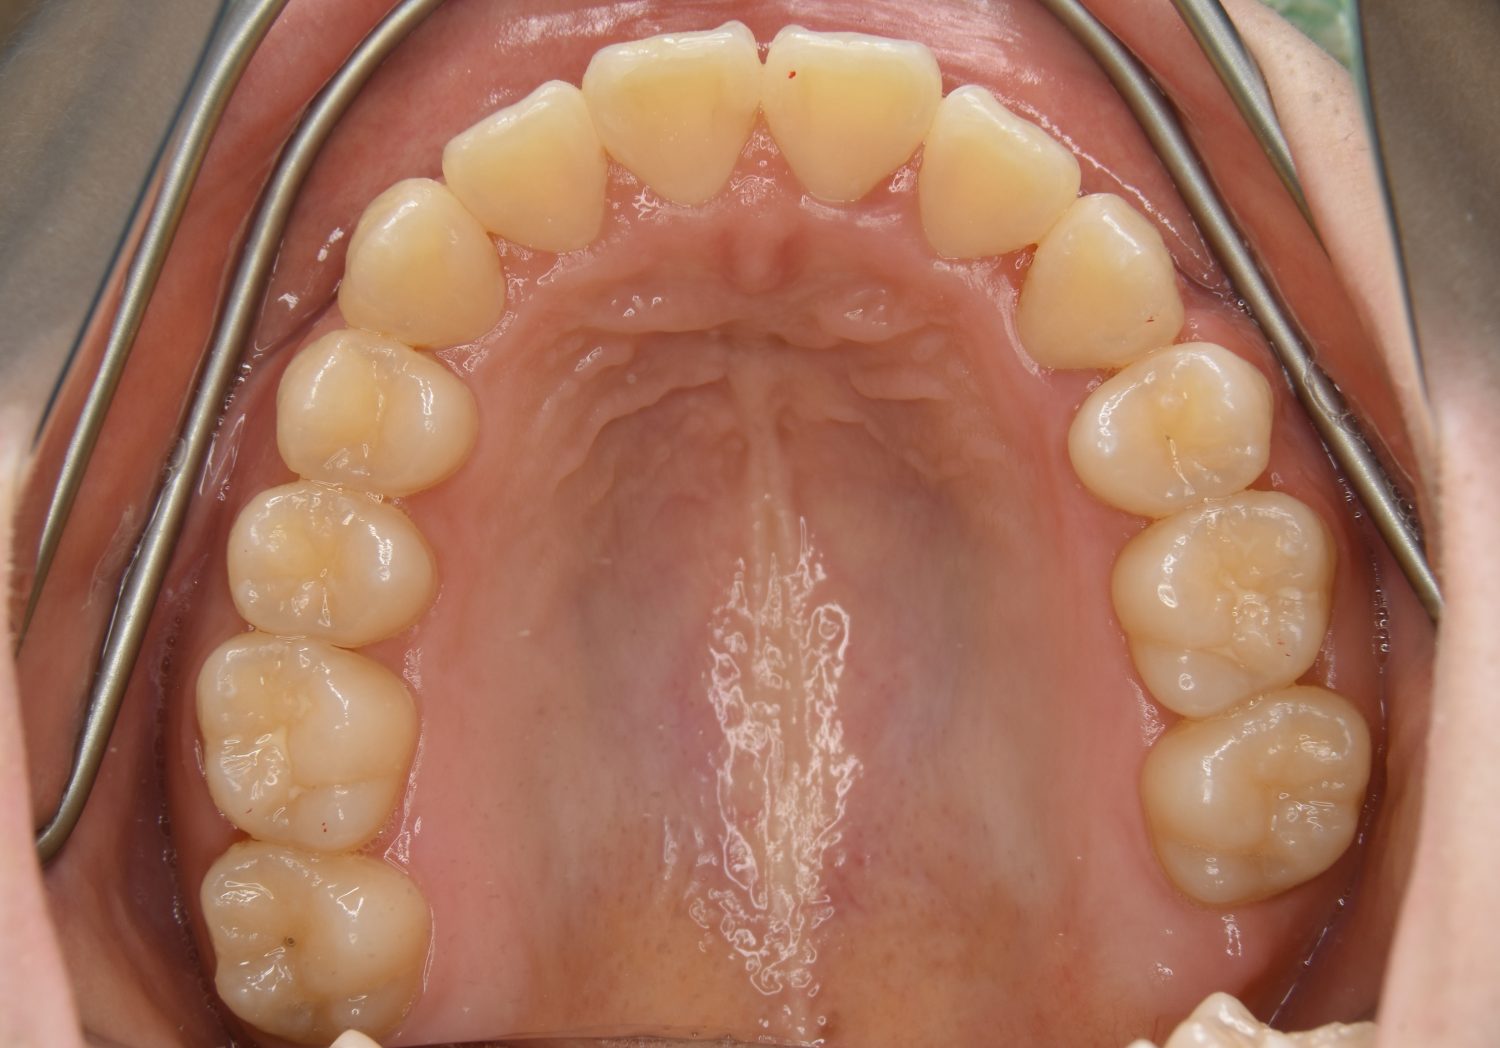

叢生の症例紹介②

Before

After

主訴

歯の凸凹を治したい。

治療内容

アライナー(インビザライン)にて非抜歯で治療を行いました。

上下前歯部に叢生(凸凹)が認められる状態でした。歯列の遠心移動を行うことで機能面および審美面が改善されました。